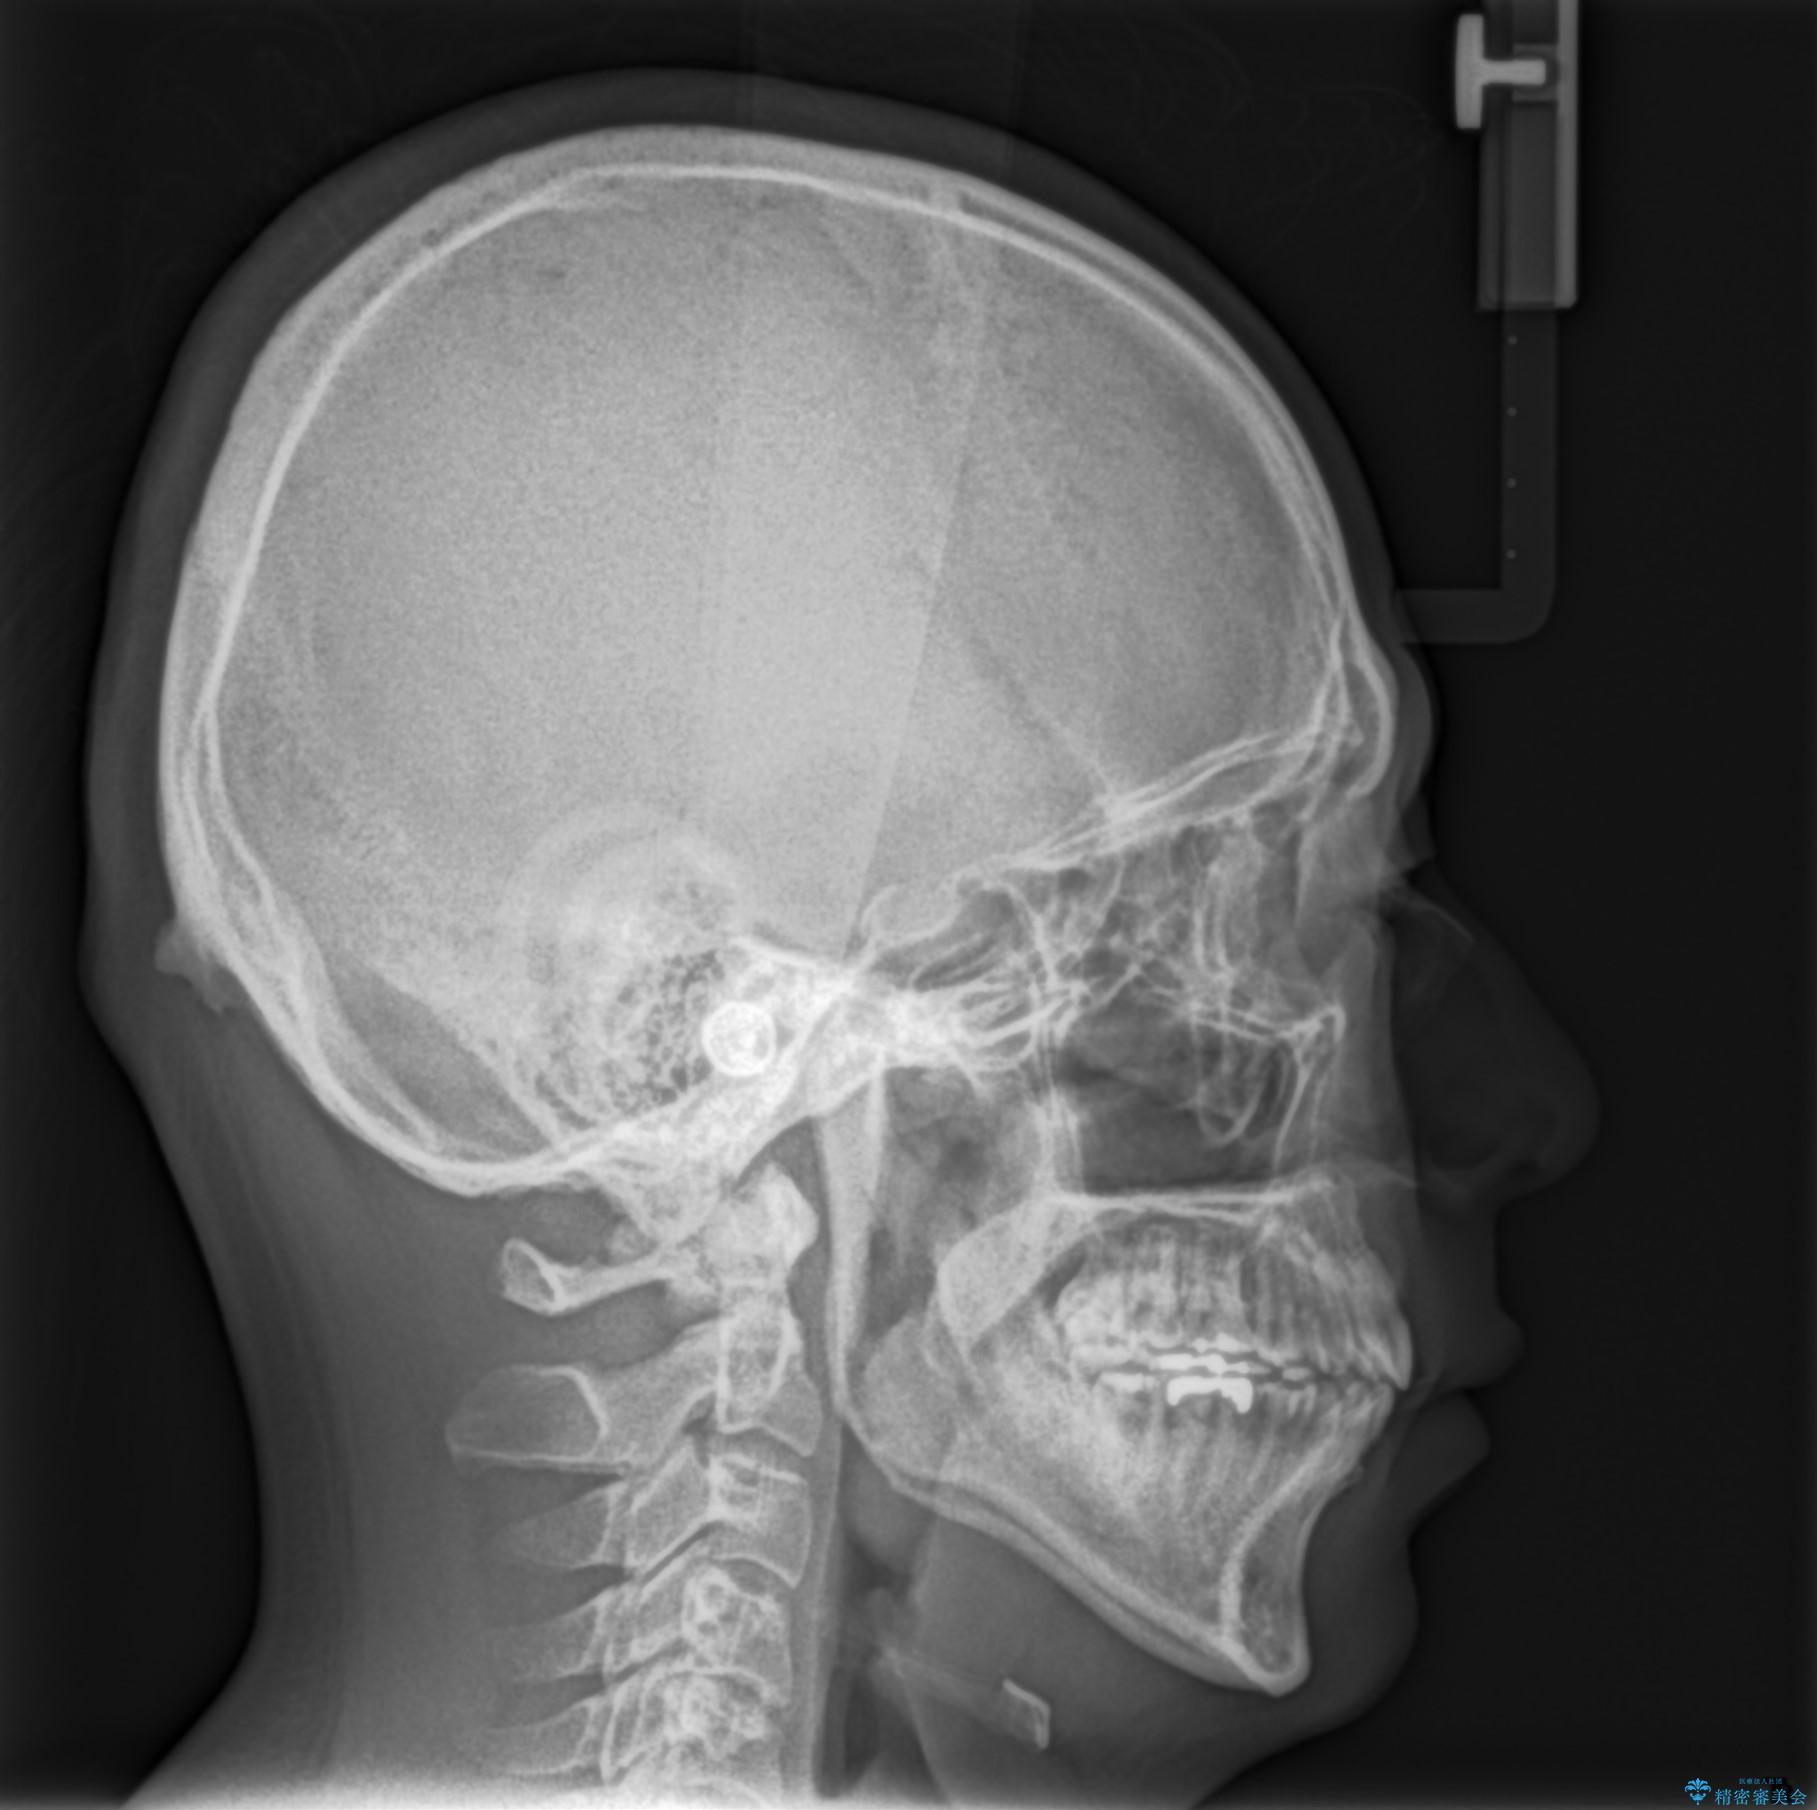

- 出っ歯が気になるとのことで来院されました。

上顎の前から4番目の歯を両側、合計2本抜歯して矯正する計画としました。

目立たない装置がご希望でしたので、上下裏側ワイヤー装置を選択されました。